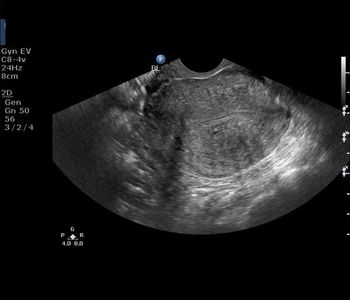

What is your diagnosis in this woman who underwent a routine pelvic sonography for non specific complaints?

There is a clearly defined rounded mass just below the endometrial stripe of the uterus. The endometrium itself appears normal in thickness ruling out hyperplasia.The mass is within the uterine fundus and body ruling out a cervical mass.